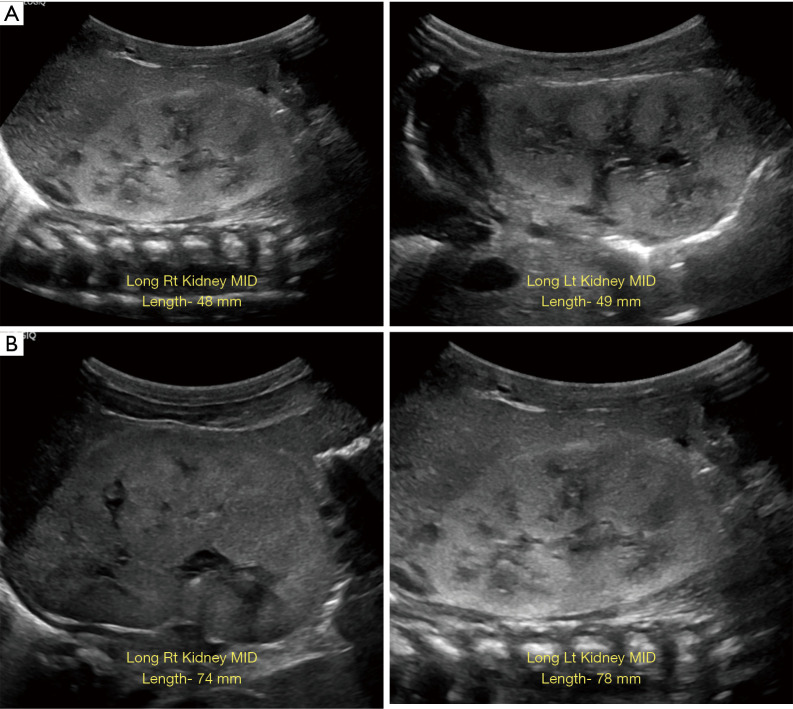

Case description: We describe the salient features of a newborn with CNF and multiple fetal anomalies based on clinical risk factors discovered by ultrasound (US) and X-rays, which include cardiomegaly, polycystic kidney disease, and renal dysplasia. Biochemical tests showed substantial proteinuria and excess protein in the urine detected at birth; this condition caused albuminuria, hypoalbuminemia, edema, and additional symptoms. The patient underwent treatment to reduce the risks of proteinuria, hypertension, infection, and other symptoms. The next generation sequencing (NGS) analysis revealed that the infant had five previously unreported heterozygous missense variants classified as VUS in NPHS1, NUP160, ALG1, and CRB2. The NPHS1 c.2150A>G and CRB2 c.1654G>T may lead to defects in the CTCF (CCCTC binding factor) and exonic splicing enhancer (ESE) motifs, respectively, which could account for the observed clinical features in the newborn.